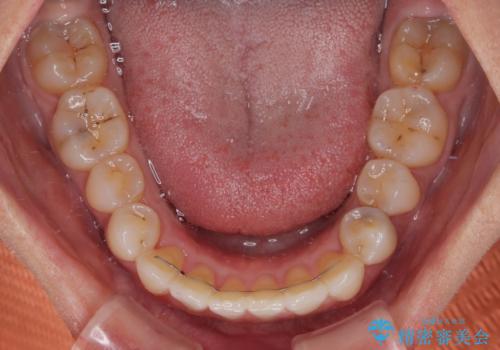

下顎前歯は後戻りを起こしやすいため、舌側を細いワイヤーで固定し、マウスピース型リテーナーで保定を行うこととしました。